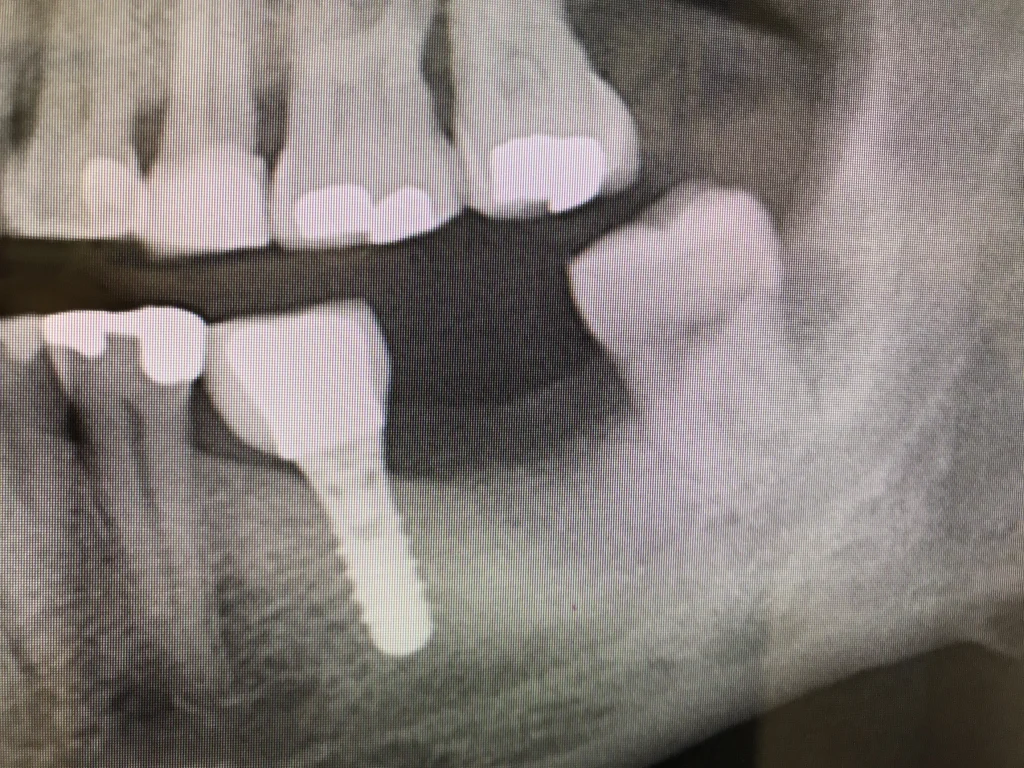

• IMPLANTE DENTALES:

• CON CARGA PROTÉSICA DIFERIDA (3 MESES)

• CON CARGA INMEDIATA (1 SEMANA)

• INMEDIATOS DESPUES DE EXTRACCION

• REGENERACION DE HUESO EN CASO DE DEFICIENCIA PARA COLOCACIÓN DE IMPLANTES:

• ELEVACIÓN DE SENO MAXILAR

• REGENERACIONES VERTICALES Y HORIZONTALES

• TRATAMIENTO DE LA REABSORCIÓN OSEA QUE AFECTA A ALGUNOS IMPLANTES (PERIMPLANTITIS)